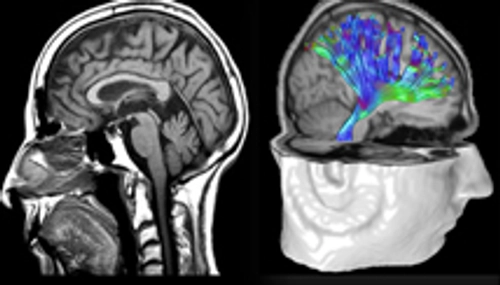

research - brain nerves

ADHD Research